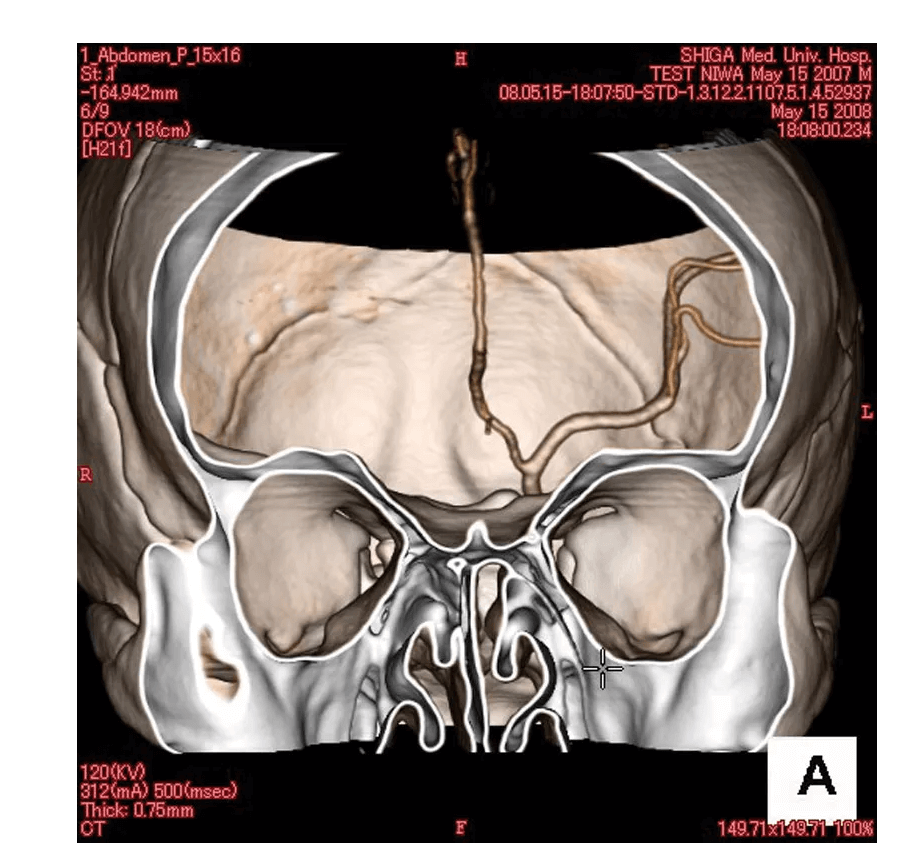

Das Angiographie Kopfmodell ist ein hochpräzises Trainingsmodell, das einen synthetischen Schädel in einen Kunststoffkopf integriert. In der linken Schädelhälfte sind die vordere und mittlere Hirnarterie nachgebildet und mit Kontrastmittel gefüllt, um realistische Trainingsbedingungen für die Angiographie zu schaffen. Die simulierten Arterien haben einen Durchmesser von 0,5 mm bis 4 mm und ermöglichen so eine detaillierte Untersuchung und Diagnose von Gefäßstrukturen im Gehirn. Dieses Modell ist besonders geeignet für medizinische Fachkräfte, die ihre Fähigkeiten in der Angiographie und Bildgebung von Gehirngefäßen verbessern möchten.

Präzise Nachbildung der vorderen und mittleren Hirnarterien im synthetischen Schädel

Arterien mit Durchmessern von 0,5 mm bis 4 mm für detaillierte Bildgebungstraining

Mit Kontrastmittel gefüllte Arterien ermöglichen realistische Angiographie-Simulationen